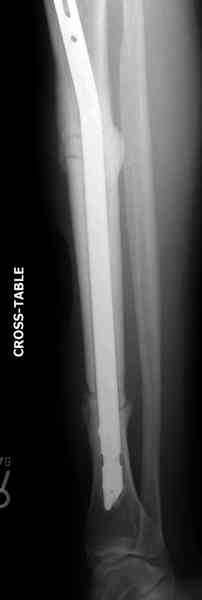

conference мы разбирали похожий случай, ложный сустав большеберцовой кости после резекции опухоли.

К нашему онкологу-ортопеду обратился больной с жалобами на боли в голени, из рассказа - год назад была сделана биопсия большеберцовой кости, но название заболевания "не запомнил”.

Оперирован в военном госпитале с заменой сегмента

аллокостью большеберцовой кости и после демобилизации явился для постоянного наблюдения по месту жительства.

Наши имели проблему со сращением, пришлось им сделать динамизацию, дополнительную аутопластику.

Снимки представлены.